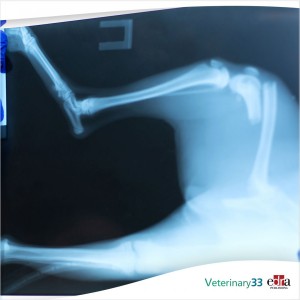

Researchers reviewed medical records of dogs surgically treated for multi-ligament stifle injury from six veterinary hospitals. Long-term follow-up on the dogs was collected from referring...